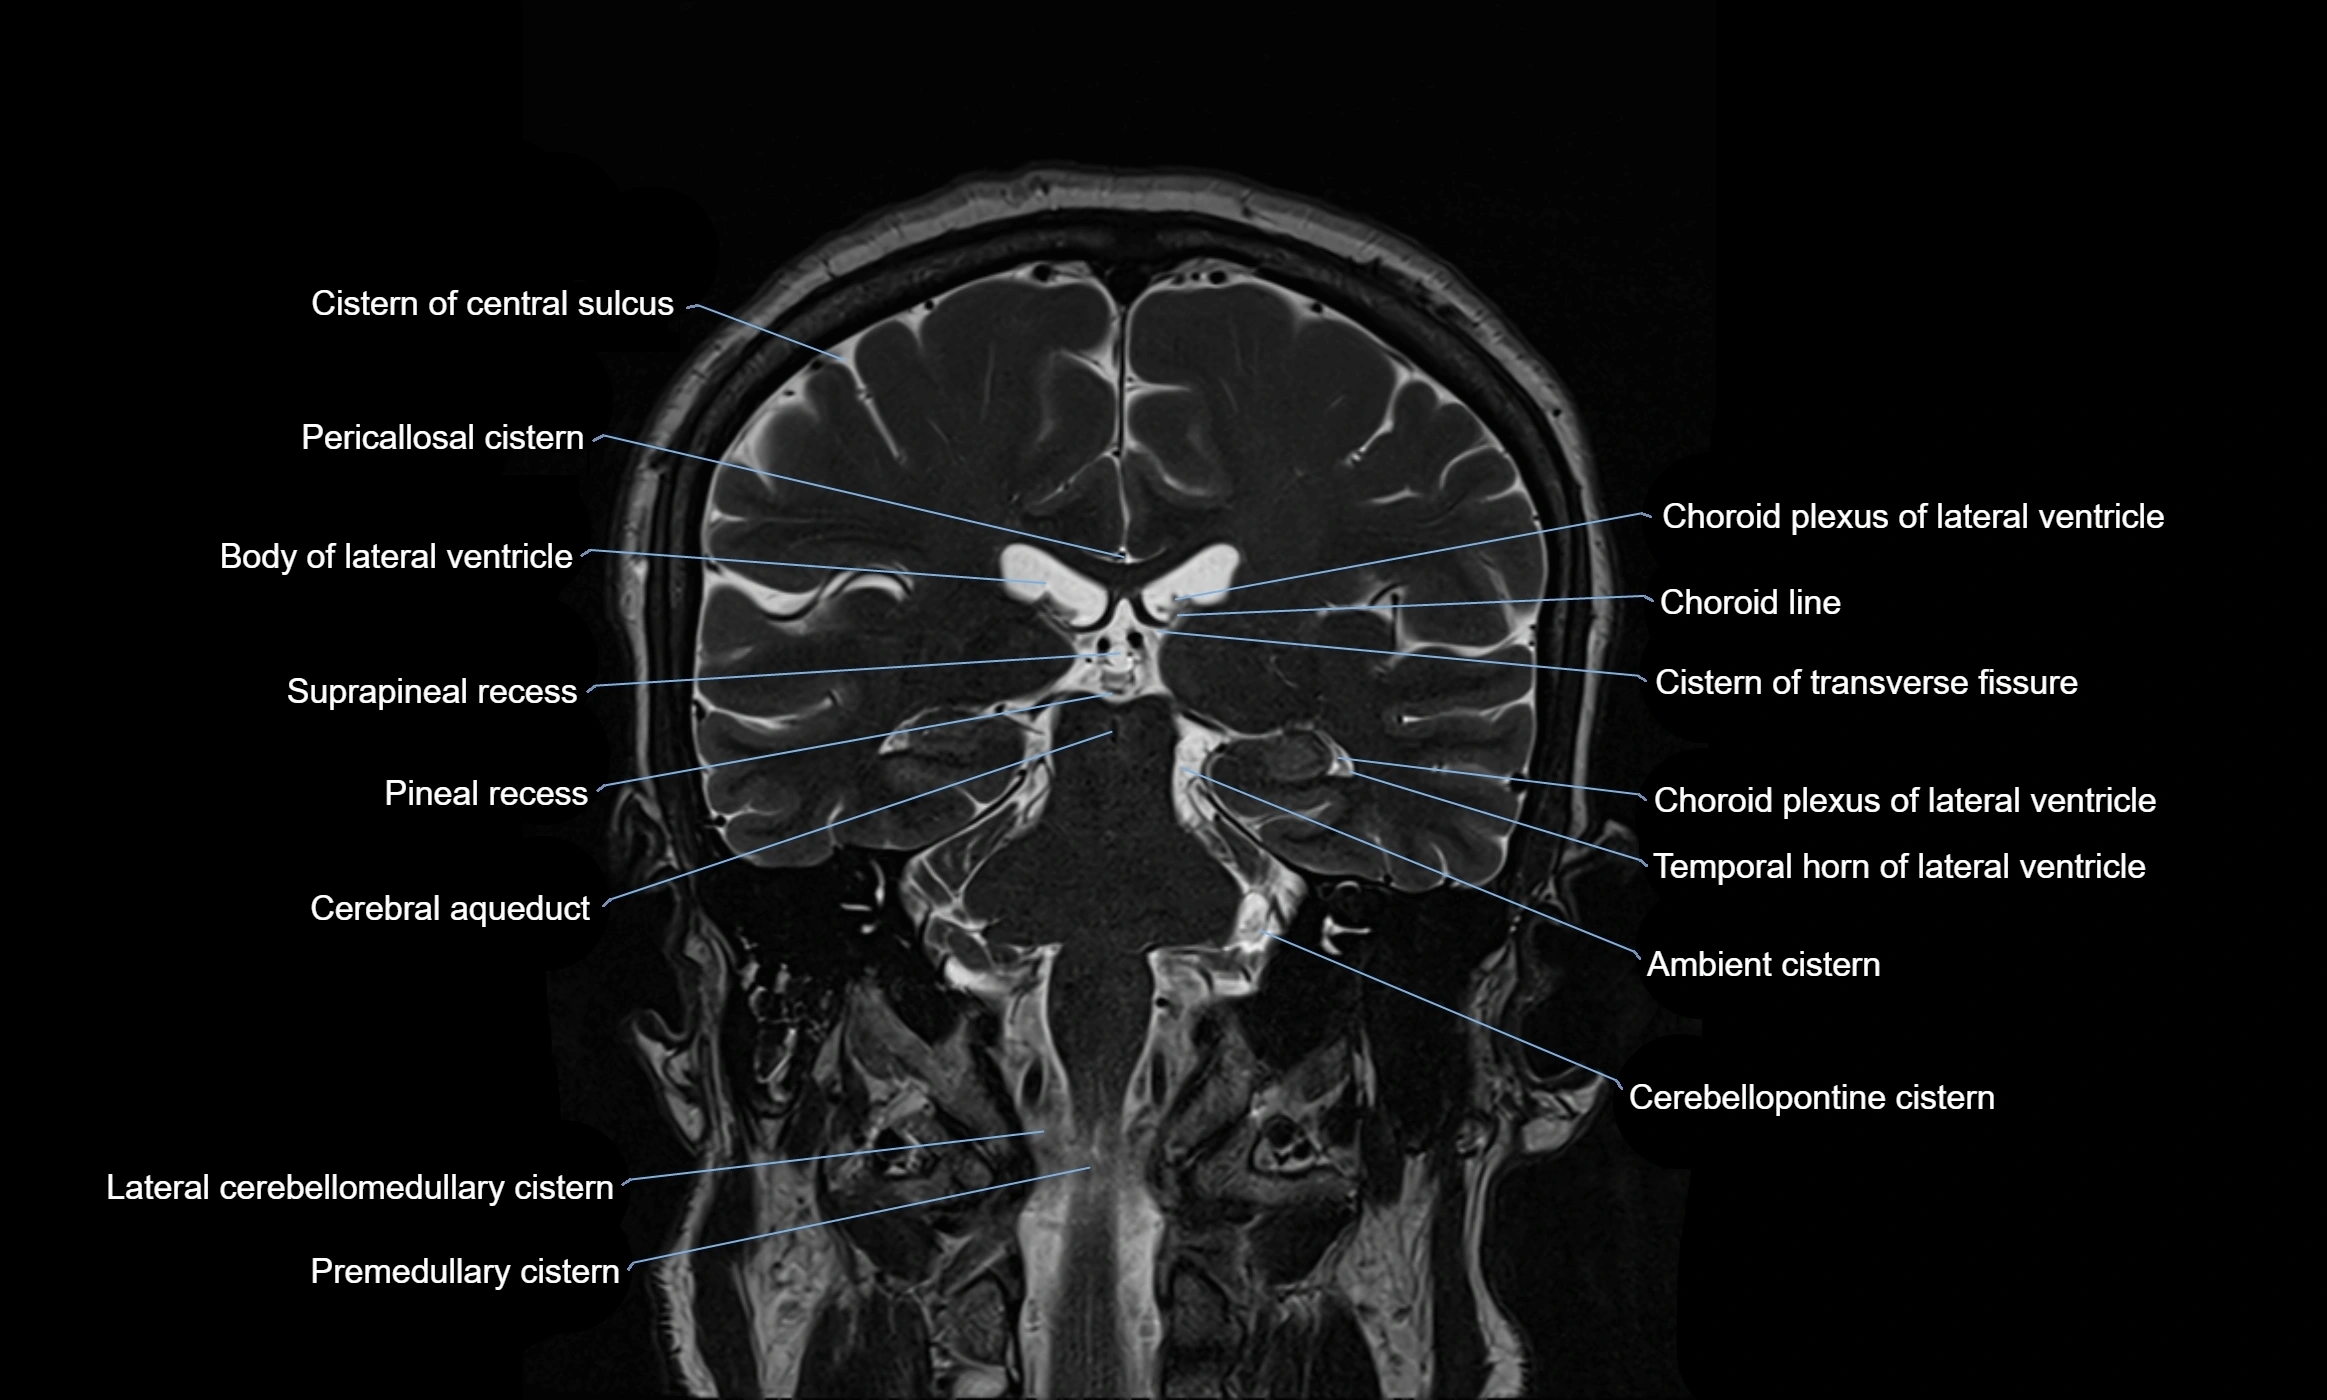

MRI images

image